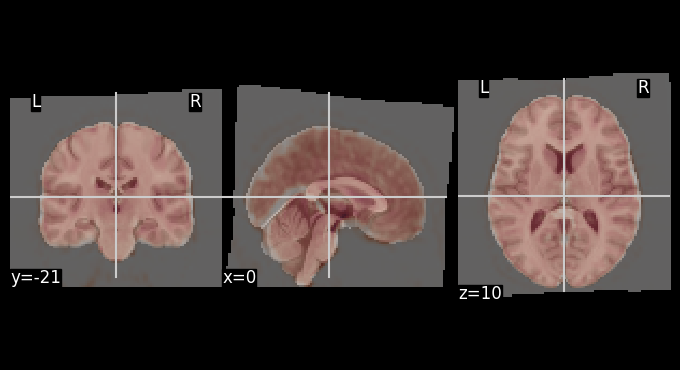

Functional registration to MNI space#

The mean BOLD image after motion correction was registered to the MNI template. The overlays below allows for visual inspection of alignment quality.

# Get mean BOLD image

mean_bold = image.mean_img(result_parallel.bold_preproc[0], copy_header=True)

# Overlay of the mean bold image on MNI background template

plotting.plot_stat_map(stat_map_img=mean_bold,

bg_img=template,

transparency=0.4,

colorbar=False)